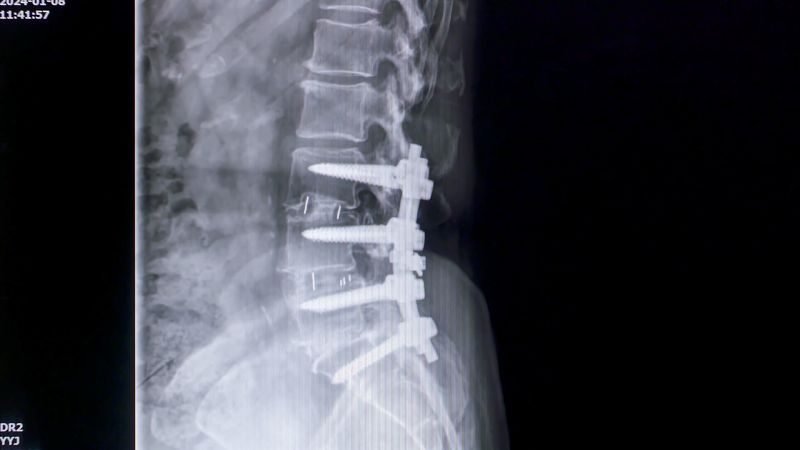

척추 수술을 앞둔 70대 여성. 한눈에 봐도 심하게 굽은 허리를 대신해 장바구니 수레가 그녀를 지탱해 주고 있었다. 검사 결과 환자는 허리가 앞으로 굽는 척추 후만증이었다. 젊은 시절부터 가사 노동으로 몸을 아끼지 않았다는 환자. 무엇이 그녀를 꼬부랑 허리로 만든 걸까?

허리를 굽게 만드는 원인은 다양하다. 그중 가장 중요한 원인은 디스크의 소실이다. 디스크는 척추뼈 사이에 위치한 물렁물렁한 연골 구조물로 척추뼈 사이에서 완충 역할을 하며 척추가 받는 전체 하중의 90%를 담당한다. 문제는 나이가 들수록 디스크가 조금씩 소실되면서 척추 앞쪽이 무너지고 척추 뒤의 체간 근육에 부담이 증가된다. 그러다 결국 근육마저 소실되면 허리가 앞으로 꼬꾸라지게 되는 것이다.